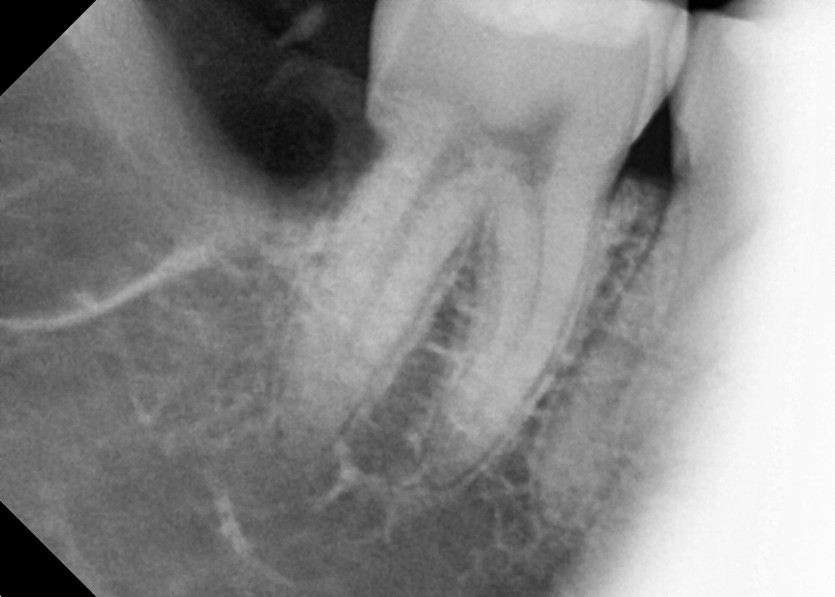

#48 사랑니 발치

구강 외과 전문의가 당일 발치했습니다.